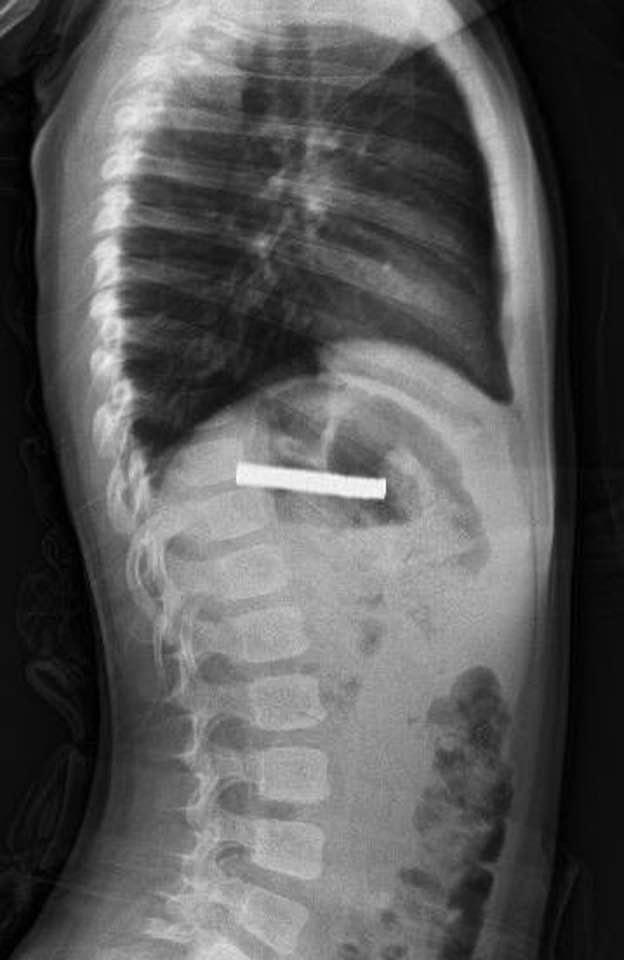

Hastanede, FÜ Çocuk Gastroenteroloji Hepatoloji ve Beslenme Bilim Dalı Başkanı Prof. Dr. Yaşar Doğan tarafından yapılan tetkiklerde mıknatısların yapışarak çocuğun yemek borusunu tıkadığı tespit edildi.

Doğan ve ekibi tarafından yapılan müdahaleyle çocuğun yemek borusundaki mıknatıslar başarılı bir şekilde çıkarıldı.

Yapılan operasyon hakkında bilgi veren Doğan, "Tabi bu mıknatıslar uzun süre hastanın yemek borusunda kaldığı için biraz hasar bırakmıştı. Çok güçlü mıknatıslardı. İşlemin kolay yapılabilmesi için mıknatıslar yemek borusundan mideye alındı, mideden özel bir fileyle çıkarıldı. İşlemden sonra hastayı gece boyunca gözlem altında tuttuk. Sabah da aile kendi isteğiyle çıkarmak isteyince, hastanın da genel durumu iyi olduğundan taburcu ettik." dedi.